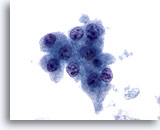

画像 2: 肝FNA – 良性肝細胞

反応性変化を来した良性肝細胞の集塊。細胞境界が明瞭な立方形の細胞が認められます。不透明な細胞質には空胞が認められるものもあれば、幾分顆粒状を呈するものもみられます。辺縁部は擦り切れた状態を呈しています。核はわずかに大小不同で、二核を有する細胞も認められます。小型の核小体がみられます。

40倍

画像 2

肝FNA – 良性肝細胞

反応性変化を来した良性肝細胞の集塊。細胞境界が明瞭な立方形の細胞が認められます。不透明な細胞質には空胞が認められるものもあれば、幾分顆粒状を呈するものもみられます。辺縁部は擦り切れた状態を呈しています。核はわずかに大小不同で、二核を有する細胞も認められます。小型の核小体がみられます。

40倍